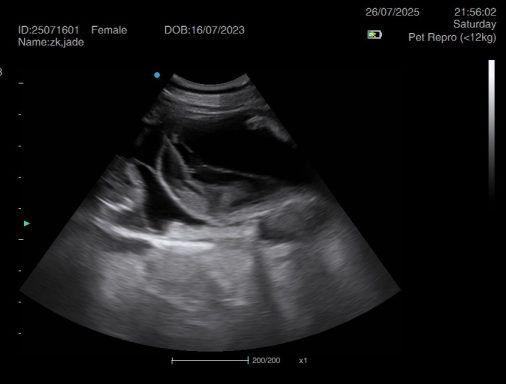

Ultrasound pregnancy scanning is a safe, non-invasive way to confirm pregnancy in dogs and cats, offering breeders and pet owners peace of mind and vital information to support responsible care. It allows us to detect gestational sacs, assess foetal development, and estimate litter size—all while ensuring the wellbeing of the animal.

Pregnancy can sometimes be detected as early as Day 18 post-mating, but scanning at this stage is not routinely recommended. Embryos are still developing and may not be clearly visible, and there is a natural risk of embryo resorption, which can lead to misleading or inconclusive results.

For the most accurate and reliable scan, we advise booking between Day 25 and Day 32, when pregnancy is more easily confirmed and foetal structures are clearer. If an early scan is performed and no pregnancy is detected, we offer a FREE complimentary re-scan after 7 days at the clinic to ensure clarity and support informed decision-making.

Our approach balances early insight with ethical care—always prioritizing the comfort of the animal and the accuracy of the results.

Gallery